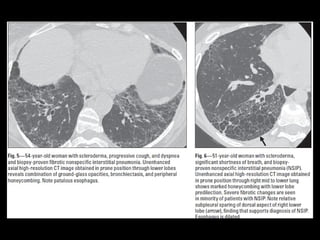

DD UIP CT

• AR, Esclerodermia (esófago dilatado)

UIP TC • Fibrosiscon áreas normales. • Disminución de volumen pulmonar • Opacidades reticulares • Vidrio esmerilado • Predominio en regiones basales y subpleurales • Distorsión arquitectónica con bronquiectasias por tracción secundaria a fibrosis. • Panal de abejas (2-20mm) • Linfoadenopatías mediastínicas pequeñas.

DD UIP CT •AR, Esclerodermia (esófago dilatado) • Asbestosis ( derrame pleural, bandas parenquimatosas) • Neumonitis por hipersensibilidad crónica: fijarse en signos de atrapamiento aéreo, Respeto de bases o cuando hay nódulos centrolobulillares. • Sarcoidosis terminal: fibrosis en segmentos posteriores de lóbulos superiores o perihiliar, o nódulos perilinfáticos. • NSIP • Complicaciones: • Exacerbación, DAD • Cáncer pulmonar 10-15% bases

NSIP • + asociadoa otras condiciones esclerodermia, poliomiositis, dermatomiositis, toxicidad a drogas, inmunodeficiencia. • Mejor pronóstico • 40-50 h=m

NSIP TC • Vidrioesmerilado bilat y simétrico, LS Reticulación fina, BQ por tracción, disminuciónd e volumen pulmonar, panalización leve Consolidaciones Exacerbaciones menos comunes que FPI • Pronóstico depende del grado de fibrosis • Celular: 100% sv Fibrótico: 5 años SV